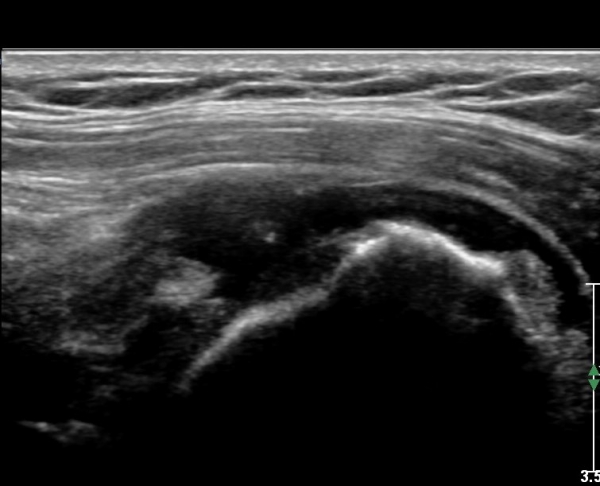

Å½ÃËÀÚ¸¦ Á»´õ ¸»´ÜÀ¸·Î À̵¿ ÈÄ(¶Ç´Â ¾Æ·¡·Î ±â¿ïÀÎ ÈÄ) ³»ÃøºÎ¸¦ Á¶ÀýÇÏ´Ï °ß°©ÇϱٰÇ

Ç¥ÃþÀ¸·Î Á¡¾×³¶³» ¼ö¾×Àú·ù°¡ °üÂûµÈ´Ù(»çÁö 3, 4). ŽÃËÀÚ¸¦ Á¶Á¤ÇÏ´Ï ÀÌµÎ¹Ú°Ç ÁÖÀ§ ¼ö¾× Àú·ù¿Í

Á¡¾×³¶³» ¼ö¾×Àú·ù°¡ °üÂûµÇ¾î Á¡¾×³¶¿°°ú Ȱ¾×¸·¿°ÀÌ ÀÖÀ½À» ¾Ë ¼ö ÀÖ´Ù(»çÁø 5).